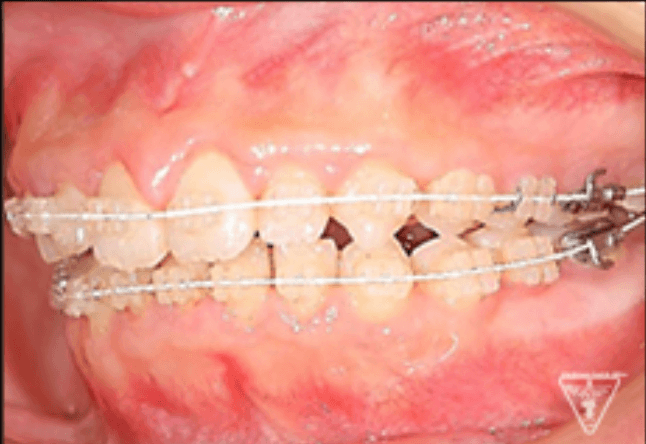

矯正器具 装着時の治療過程

初期